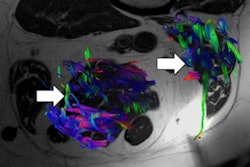

To measure muscle changes, the researchers tracked the anterior-posterior and lateral-lateral diameters of the muscles, as well as their cross-sectional area, which is calculated from the perimetral contour of the muscle area and is considered to be proportional to the total mass of the skeletal muscle.

Ultrasound evaluation showed that rectus femoris muscle mass changed significantly over the course of patients' ICU stay, with anterior-posterior diameter decreasing progressively between day 5 and day 20. Lateral-lateral diameter did not show a progressive decrease, but the difference between day 0 and day 20 was significant, the group noted. The cross-sectional area of the rectus femoris muscle progressively decreased as well, particularly between day 5 and day 20, with an overall loss of cross-sectional area of 45%.

As for anterior tibialis muscles, the anterior-posterior diameter decreased progressively over the course of the ICU stay for all patients, although lateral-lateral diameter did not decrease significantly. Overall loss of cross-sectional area for the anterior tibialis muscles was 22%; however, this was not statistically significant, according to the researchers.